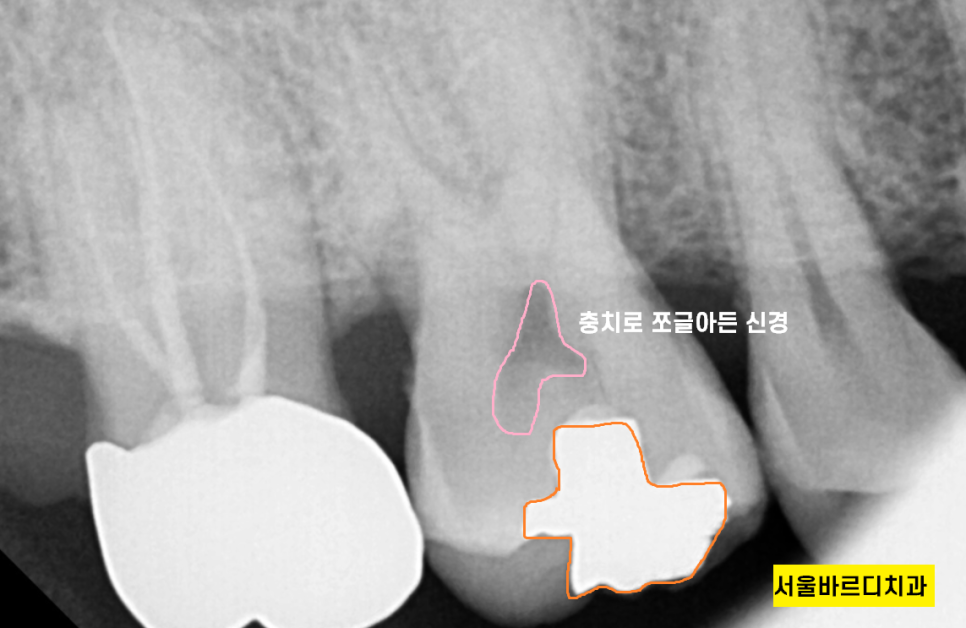

이차 충치가 발생,

신경이 쪼글아 들때까지 모르셨네요.

놀랍게도 충치가 신경까지 진행되지 않으면

통증이 없습니다.

때문에 아파서 오면 치과는 늦는다는 얘기가

여기서 나왔어요~

충치가 치아 대부분 부위에 있어서

신경치료를 하는 수 밖에 없었어요.